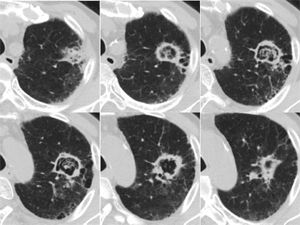

両肺に数少ないが多発結節(小葉との関係は判断困難)の出現、出現速度は速く、増大経過(LVFX抵抗性)

2010.06.2) 初診から5週後

増大したものの一部に空洞形成、左上区の最大のものの空洞内には同心円状・索状構造がみられる